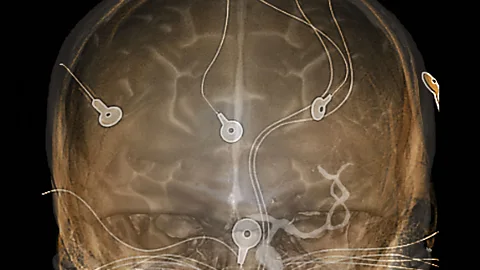

SPLBut that wasn't getting us any closer to looking at the brain in action. It was only in the 1920s that scientists began to read the brain’s electrical signals. This gave them the first insights into the electrical activity occurring inside an actual living brain, a technique called electroencephalography (EEG).

When it began, it was quite an invasive technique. Behind the scenes at the Science Museum, in their enormous storage warehouse, Dabin showed me an early EEG machine:

EEG machines were used for both reading the brain’s signals but also to stimulate the brain with electricity.